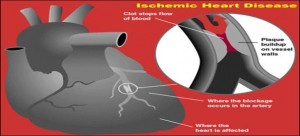

1. Ішемічна хвороба серця 13%

Причини: Куріння; Сидячий образ життя; гіпертонія; Цукровий діабет; атеросклероз; Скорочення стовбурових клітин; скорочення теломер